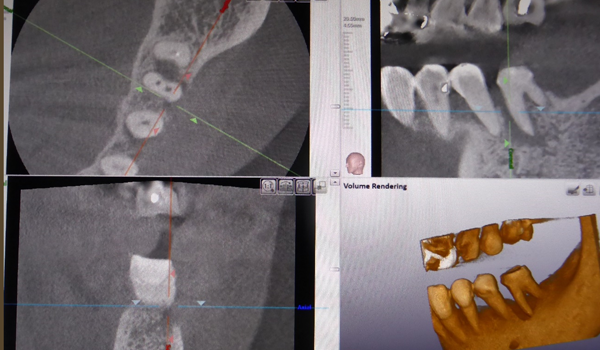

歯の根の治療

何か月も治療が長引くケースの原因究明のためや、曲がった根の治療を行うときに根の長さや向きを調べるなど、様々な状況で利用します。

根のために使用するCTは細かいところまで映る必要があります。 よってインプラント治療を主に診断することを目的に作られたCTや医科用CTでは根の治療時に診断するのに利用するのは難しく、高性能の歯科用CTが必須となります。

歯周病治療

CTを撮影することで、骨の状況を正確に確認できます。

現在、様々な方法で骨の再生が可能となってきております。 再生療法の成功率を高めるためにCTは重要な役割を果たします。

歯根破折治療

通常のレントゲンでは映らないようなヒビもCTに映ることがあります。

どうしても歯を抜きたくない場合ヒビを修復して歯を持たせることが場合によって可能であり、その折にCTを撮影することがあります。